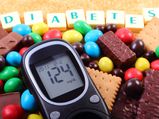

Type 2 Diabetes Has Become A Major Disease: Know About Its Causes, Symptoms & Prevention

Type 2 Diabetes Has Become A Major Disease: Know About Its Causes, Symptoms & Prevention -